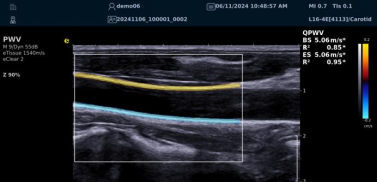

QPWV 彩色脉搏波传导速度定量技术

QPWV 技术是新航娱乐医疗的极速脉搏波速度测量技术,对脑卒中诊疗优势明显:

? 可进行动脉壁运动速度 - 时间彩色成像,直接测量单点脉搏波传导速度及相关参数(如 BSES 时的速度及标准差)。

? 能在血管内中膜增厚前的内皮功能不全阶段检测异常,对早期动脉硬化评估极具临床价值。

? 操作简单直接,无需附加设备,影响因素少,检测快速、重复性和稳定性高。